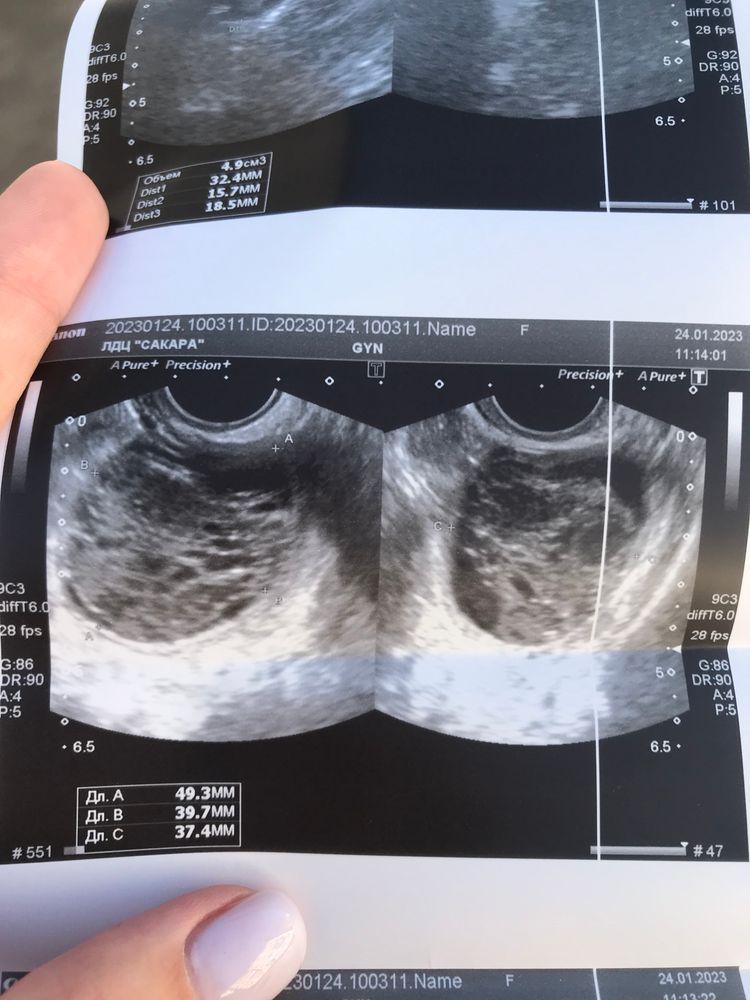

26 июня у меня пошли месячные на 26 день цикла( хотя обычно он 35 дней), в это же время на узи обнаружили кисту в яичнике 5 см 😬 мультифолликулярные яичники, андрогения - как сказала врач